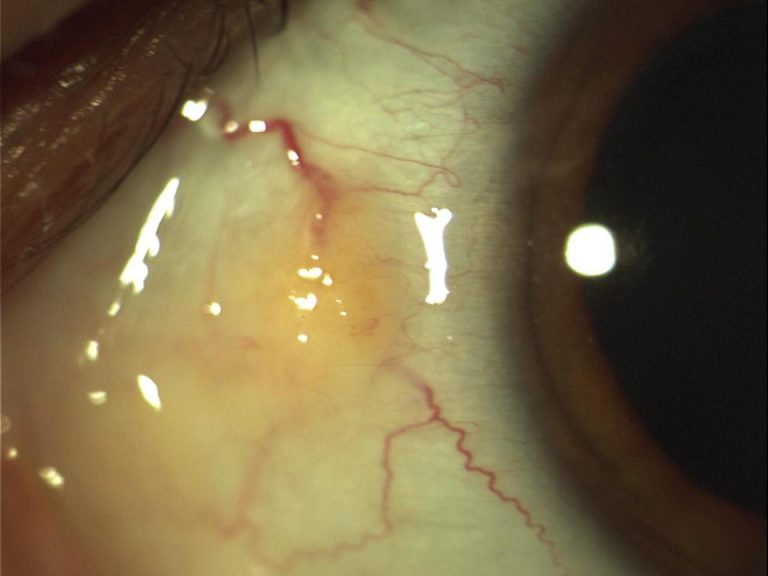

A pinguecula (pin gwe’ cue la) is a benign, yellowish growth that forms on the conjunctiva. They usually grow near the cornea on the nasal side. Pingueculae (plural form of pinguecula) are thought to be caused by ultraviolet light and are most common among people who spend a great deal of time outdoors.

This growth does not affect vision, but may cause irritation if it becomes elevated. In rare cases, the pinguecula may gradually extend over the cornea, forming a pterygium.

Pingueculae can often be seen with the naked eye; however, the eye care practitioner diagnoses the growth with a careful examination with a slit lamp microscope.

Because of their benign nature, pingueculae rarely require treatment. Occasionally, the growth may become inflamed, causing irritation and dryness. The eye care practitioner may prescribe artificial tears for lubrication and mild anti-inflammatory medication to reduce swelling.